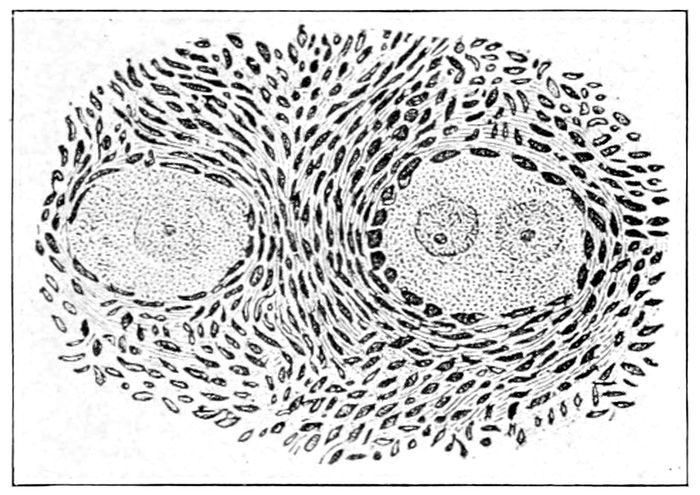

Fig. 14.—Human spermatozoa. h, head; c, intermediate portion; t, tail. (Williams.)

Conception, or Fertilization.—This is the process

wherein the male element (spermatozoon) meets and

unites with the female egg. From what is known from

investigations of lower animals, this meeting usually

The spermatozoon makes its way upward from the

vagina by means of its tail. This activity, like the tail

of a fish, or snake, or as a boat is sculled, drives the cell

37forward through the thin layer of fluid that covers the

mucous membranes.

The arrow-shaped spermatozoon travels at a rate that

completes the passage to the ovary in twenty-four hours,

but spermatozoa may lie in wait for the egg a considerable

time, as is shown by the fact that they have

been found alive in Fallopian tubes removed three and

a half weeks after copulation. As soon as the male and

female elements approach each other, they exercise a

powerful magnetic attraction, which draws them together,

and as soon as they touch, the two cells unite

and the spermatozoon almost immediately disappears.

Only one spermatozoon is required for the fertilization

of an egg, and hence enormous numbers must perish

without achieving their destiny.